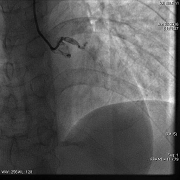

◆冠脉造影结果

◆左主干未见斑块及狭窄,前降支近段可见斑块,狭窄约50-60%,中段分出第二对角支后完全闭塞,血流Timi0级,回旋支中段及远段斑块,狭窄约80-90%,血流Timi3级,右冠全程管壁不规则,斑块狭窄约30-40%。

冠脉造影(左冠)

罪犯血管:左前降支